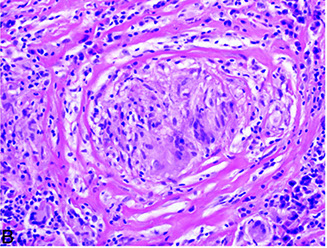

Sacroidosis. Granuolomas are distributed along the pleura (top), interlobular septum (arows) and bronchovascular bundles (arrowhead). ("lymphangitic distribution"). The inflam is localized to the granulomas and does not extend intto the adjacent lung parenchyma

Sarcoidosis. Well-formed, non-necrotizing granuloma surrounded by characteristic concentric fibrosis

A. Asteroid body (endogenous) in sarcoidosis. B crystalline inclusion (endogenous) in sarcoidosis (the inclusion is birefringent [inset])

Sarcoidosis

Multisystem granulomatous dz c no known etiology; mostly in middle-aged black women

- can present c perihilar nodal dz w/o lung involvement, diffuse lung dz w/o LN involvement on imaging, or a mix of both

-- can be dx'd w/o bx if pt has Lofgren's syndrome, Heerfordt's syndrome, or asx bilateral hilar lymphadenopathy

Imaging: lambda or panda sign on gallium uptake

Histo: patchy, nonnecrotizing granuloma c epithelioid cells, Langerhans GC, activated macrophages, Th cells

- granulomas usually in interstitium of lung (not in air spaces) or around vessels; follows lymphatics

- necrotizing sarcoid granulomatosis is diffusely infiltrative and destructive

- Hamazaki-Wesenberg bodies: small oval tan bodies in sinusoidal spaces of LNs that are Giemsa (+)

- other intracytoplasmic "bodies" made of calcium are asteroid bodies, Schaumann bodies and conchoid bodies